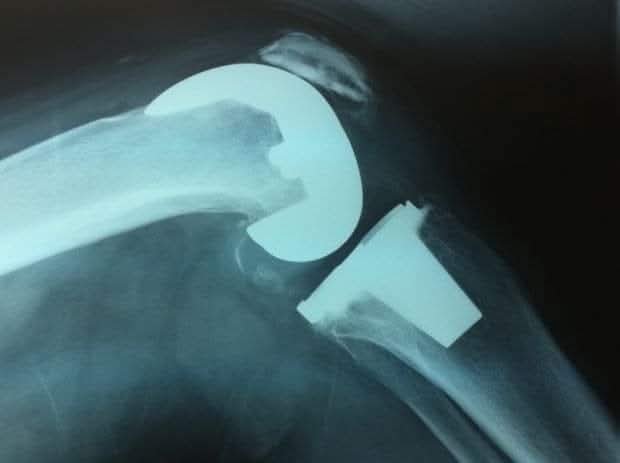

Rayos X

Análisis diagnóstico